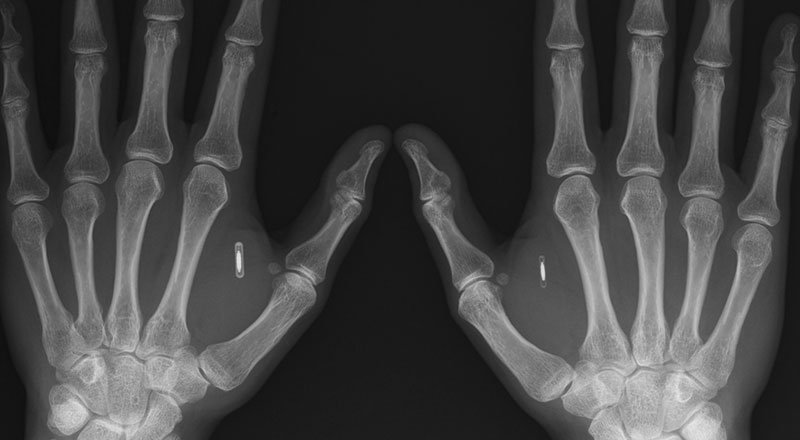

Biohackerlar cihazları kontrol etmek ve diğer cihazlarla iletişim kurmak için vücutlarını kullanma konusunda oldukça ileriye gidebiliyor. Günümüzde bu çok ekstrem gibi görünse de ilerleyen yıllarda hepimiz için birer "normal" olabilir. Biohacker Brian McEvoy kuzeyi bulduğunda hatırlatması için derisinin altına bir pusula eklemiş. Bu örneğe benzer bir çok NFC ve RFID çipini vücudunun farklı bölmelerine ekleten insan bulunuyor dünyada. (Birer cyborg olma hayaliyle yaşadıklarını düşünüyorum.)